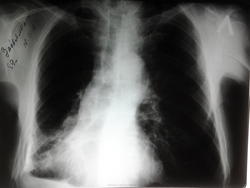

плеврит?

Пациент 89 лет,жалобы на кашель,отдышка

Смещение сердечной тени вправо и уменьшение фронтального размера нижних отделов правого легкого свидетельствуют об ателектазе правого легкого. Жидкость в плевральном синусе справа может быть плевритом. Снимок "перебит". Боковая проекция - стандарт исследования.

Без бока больше данных за спайки, шварты и фиброз.

Уменьшение нижней доли правого легкого, смещение тени средостения вправо, подтянутость правого корня книзу, кнаружи, дополнительное тенеобразование в проекции нижнедолевого бронха справа, жидкость в плевральной полости-само собой напрашивается вывод.

По одному прямому легко можно ошибиться,посчитав изменения фиброзом и спайками.Средостение тянет вправо-ищем онкологию.Правый бок нужен.

Настораживает на онкологию. Но могут быть и фиброз со спайками. Переделайте уже завтра и прямой с меньшей экспозицией.

Помимо смещения, верхний отдел средостения выглядит очень странно, возможно там все в увеличенных лимфоузлах, трахея отклонена, бифуркация потерялась. Онкология какая-то

А я в другую сторону: возраст приличный, перенесенный плеврит, плеврофиброз, пневмофиброз, рек. беседа с пациентом, поднять амбулаторную карту и флюороархив, по-возможности.